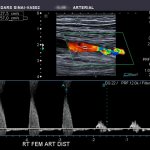

• Электрокардиография. Показывает функциональное состояние сердечнососудистой системы. Может назначаться после нагрузки (велоэргометрия).

• Эхокардиография. Ультразвуковая методика визуализации тканей. Все пороки становятся хорошо видны.

По мере необходимости показана томография сердца, коронография. Возможно назначение допплерографии сосудов (УЗДГ).